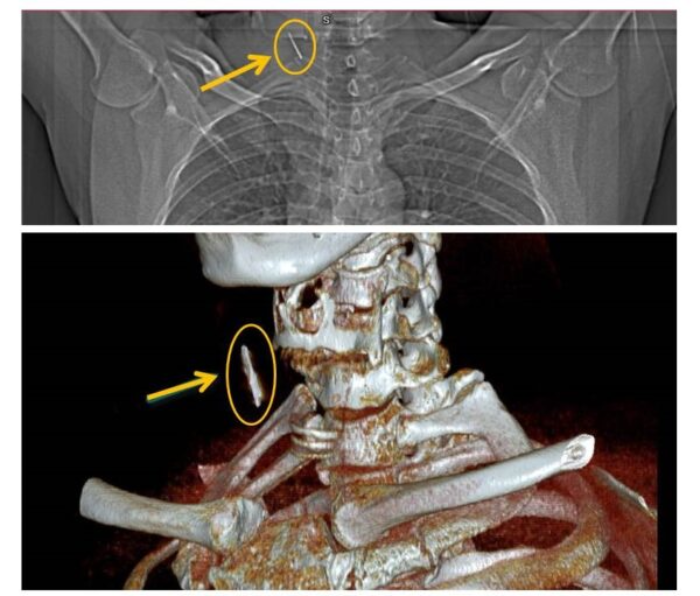

Đi khám sức khỏe tại Bệnh viện đa khoa tỉnh Phú Thọ, anh T.H.C (43 tuổi, trú tại Thụy Vân, Việt Trì) bất ngờ khi được bác sĩ thông báo nghi ngờ có dị vật cắm sâu ở vùng cổ bên phải sau khi xem phim chụp X-quang. Bác sĩ chuyên khoa Tai Mũi Họng đã chỉ định cho bệnh nhân đi chụp CT. Kết quả khẳng định có dị vật phần mềm vùng cổ.

Ngày 24/6, bệnh nhân được phẫu thuật mở cạnh cổ lấy dị vật ra khỏi cơ thể. Dị vật được lấy ra là chiếc đinh kim loại trong trình trạng rỉ sét, được bao bọc bởi tổ chức xơ với kích thước khoảng 2,5 cm. Sau phẫu thuật, tình trạng sức khỏe của bệnh nhân ổn định, dự kiến được xuất viện trong vài ngày tới.

Bác sĩ Đạt cho biết thêm may mắn dị vật nằm sâu giữa cơ ức đòn chũm và cơ vai móng, không làm tổn thương các mạch máu lớn nên không đe dọa đến tính mạng. Dị vật tồn tại trong cơ thể một thời gian dài có thể dẫn đến các biến chứng, nên việc phẫu thuật lấy ra là cần thiết.